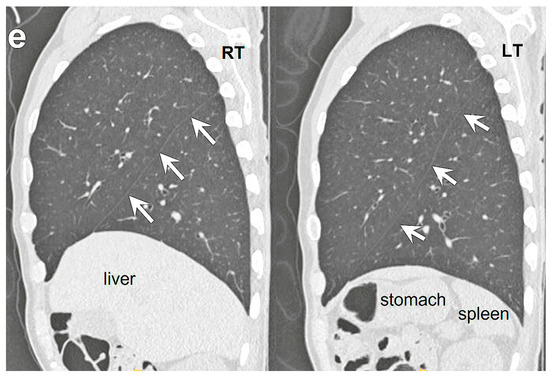

A 74 year old male patient was hospitalized with a progressive weakness of his arms that began seven months prior to hospitalization. Based on neurologic studies, he was diagnosed with amyotrophic lateral sclerosis. As he also complained of exertional dyspnea upon admission, an evaluation was performed for the presence of thoracic lesions. A chest X-ray showed unremarkable findings. A contrast-enhanced chest CT scan was also performed, showing no parenchymal infiltrates or pulmonary thromboembolism. However, there were tracheobronchial branching anomalies. At the level of the carina, an aberrant bronchus was noted, arising from the right main bronchus (tracheal bronchus) (Figure 1a). A coronal, reformatted image showed that both main bronchi were long, with right main bronchus resembling the left bronchus morphologically (Figure 1b). A reconstructed, 3D CT image of the tracheobronchial tree revealed a symmetrical bronchial branching pattern of both bronchi. Similar to the left upper lobe bronchus, the right middle lobe bronchus (B4 and B5) arose with the upper lobe bronchus (Figure 1c). A tracheal bronchus arising from the right main bronchus corresponded to a displaced apical segmental bronchus (B1) of the right upper lobe. A superimposed, three dimensional (3D) CT image of the tracheobronchial tree and pulmonary arteries showed that both upper lobe bronchi were hyparterial. The upper lobe bronchus arose below the point where the ipsilateral pulmonary artery crossed the main bronchus (Figure 1d). Both lungs were bilobed (Figure 1e). There was no minor fissure in the right lung. Further systemic evaluation did not reveal any congenital cardiovascular disease or abdominal visceral malposition. Therefore, the patient was diagnosed as having an isolated bronchial branching anomaly, left bronchial isomerism with a right-sided, eparterial tracheal bronchus. Despite bronchial anomaly, it was determined that the patient’s respiratory symptoms were attributed to progressive amyotrophic lateral sclerosis.

Figure 1.

A 74 year old man with tracheal bronchus and left bronchial isomerism. (a) An axial chest CT image with lung window setting showing an aberrant bronchus (tracheal bronchus, arrow) arising from the right main bronchus at the level of carina. (b) A coronal, reformatted chest CT image with lung window setting showing symmetrical long both main bronchi resembling the left bronchus morphologically. Right upper lobe bronchus (RUL) is located below the point where the pulmonary artery (asterisk) crosses the main bronchus as on the left (hyparterial). Note tracheal bronchus directing towards the right upper lobe. (c) Reconstructed, 3D CT image of the tracheobronchial tree revealing both upper lobe bronchi in the same position. Similar to lingular division (arrow) of the left upper lobe bronchus, the right middle lobe bronchus (RML, arrow) arises with the right upper lobe bronchus. Displaced apical segmental bronchus (B1, thin arrow) arises from tracheal bronchus. Posterior and anterior segmental bronchi (B2 and B3) arise from right upper lobe bronchus. (d) Superimposed 3D CT image of the tracheobronchial tree and pulmonary arteries (asterisks) showing that both upper lobe bronchi (arrows) are hyparterial. (e) Sagittal reformatted CT images with lung window setting showing bilobed left and right lungs (arrows indicate both major fissures). There is no minor fissure in the right lung.